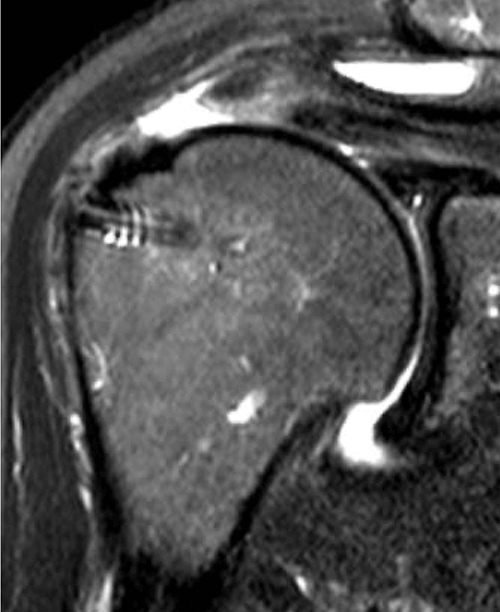

We published this case study in the JOEI (Journal of Orthopedic Experience and Innovation) Journal. We did a revision of the large type-II repair and augmented it with BioBrace®. You can see the pre-op and three-month MRI below. Still fluid in the subacromial space but that tendon is clearly coming across into the footprint. Then, an eight-month MRI shows there's no further fluid in the subacromial space and maturation of that repair across the footprint.

8 Months

This is a patient that’s been in pain for quite some time and was clinically improving. You can see the outcome scores show dramatic improvement.